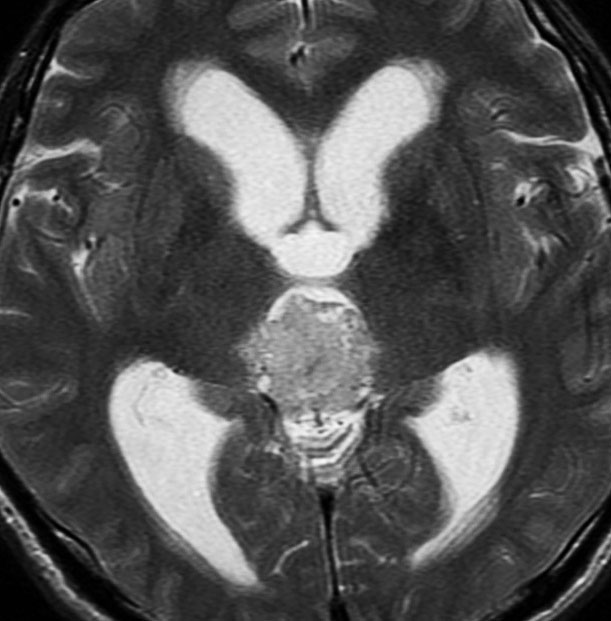

水頭症で発症した6歳児で,4cmくらいある大きな松果体芽腫でした。大学病院で第3脳室開窓術と生検術をして,脳脊髄照射30グレイ(20分割),局所60グレイ(35分割)の放射線治療が行われました。さらにシスプラチンを基剤とした化学療法が3コース行われましたが,放射線で縮小した腫瘍は少し増大してしまいました。

放射線化学療法後の画像です。腫瘍境界は不明瞭(左)で,腫瘍内出血(中央)して,左の視床に浸潤しています。かなりリスクは高いのですが,これを開頭手術で全摘出しました(右),この時点で完全寛解 CR です。この後にさらに化学療法と幹細胞移植(PBSCT,大量化学療法)が加えられました。